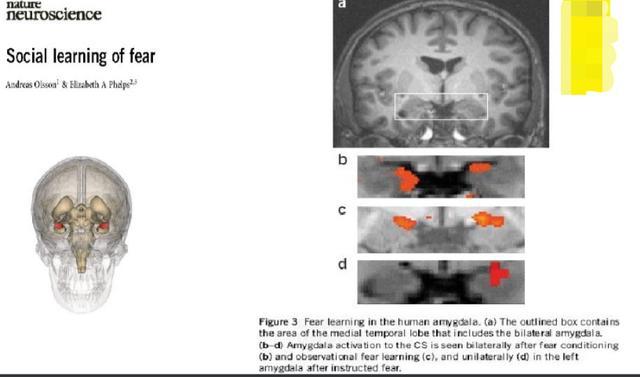

如下这张图,是人类大脑的恐惧中心部位,杏仁核所在的位置,见a图的方框位置。

本实验是请一位学生,在手上戴上放电装置,然后用核磁共振拍其大脑神经元的活化情况,每次铃声一响时,3秒后电就会出来。

b,c,d是不同情况下对应大脑的恐惧中心活化的情况。

b图是只要铃声一响,大脑的恐惧中心立即活化,也就是此时,电还没有出来,但是大脑知道电要来了,于是立即恐惧起来。

c图则是看着被电的人的大脑图,恐惧中心也是活化的,也就是看着别人被惩罚,看的人也一样恐惧。

d图则是电左边的手,大脑右边恐惧中心活化。